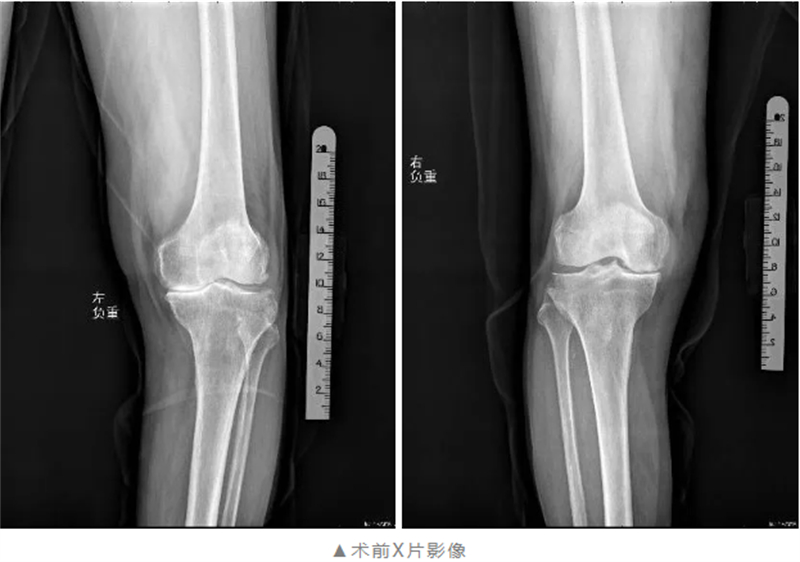

黃阿公的膝關(guān)節(jié)噩夢(mèng)始于30年前,長(zhǎng)期的膝關(guān)節(jié)疼痛逐漸導(dǎo)致他的雙腿變成嚴(yán)重的“O”型腿,每走一步都劇痛難忍。性格開(kāi)朗的他不得不長(zhǎng)期臥床,生活質(zhì)量急轉(zhuǎn)直下,身心飽受煎熬。“看著父親被病痛折磨,我們卻束手無(wú)策,心里太難受了。”黃阿公的兒子回憶道。

經(jīng)過(guò)全面細(xì)致的檢查與多學(xué)科會(huì)診評(píng)估,關(guān)節(jié)骨病科團(tuán)隊(duì)在與黃阿公及其家屬充分溝通后,制定了個(gè)性化的膝關(guān)節(jié)手術(shù)方案——雙側(cè)膝關(guān)節(jié)單髁置換術(shù),在膝關(guān)節(jié)磨損的部位植入特殊材料的“墊片”,最大限度的保留了患者的本體感覺(jué)和關(guān)節(jié)功能。